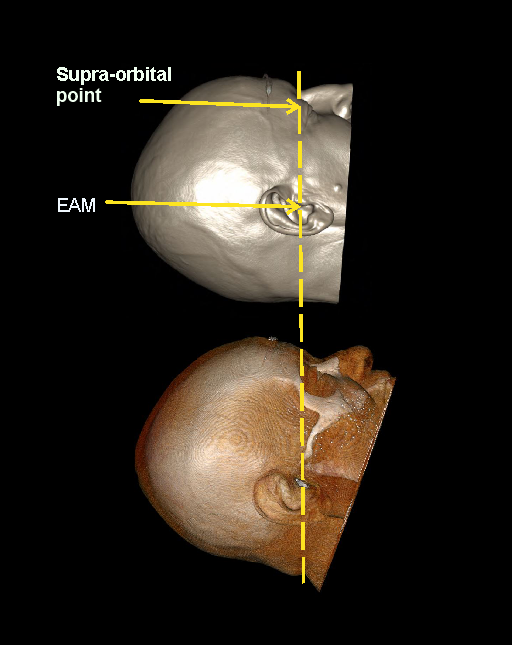

- Tilt patient’s head such that the line joining supra-orbital point and external auditory meatus (EAM) perpendicular to the floor, and ask to close the eyes.

Explanation: This method reduces eye lens dose [1 and 4].